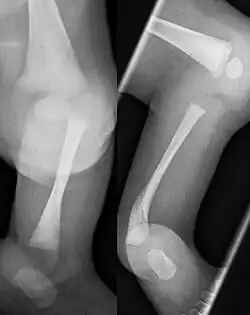

Kongenitale Tibiale Hemimelie Typ I

Kongenitale Tibiale Hemimelie Type II

Congenital Tibiale Hemimelie Typ III

Für die Behandlung gebräuchlich ist die Klassifikation nach Kalamchi und Dawe:[6]

• Typ I Aplasie der Tibia, Fuß adduziert, + eventuell fehlende Strahlen medial

• Typ II Tibia nur distal fehlend, Artikulation zum Femur erhalten

• Typ III Dysplasie der Tibia distal mit tibiofibulärer Diastase (Fehlanlage der Sprunggelenksgabel)